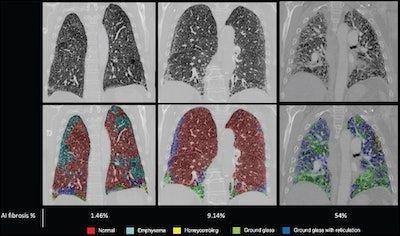

#ImagingAI algorithms not only need to be accurate, but also produce "visually verifiable" results. Looking forward to sharing @UCSDHealth #AiDALab #DeepLearningStrain at the upcoming @SCMRorg meeting. What abnormality do you see in this strain rate map? @RSNA @NASCISociety

For #ImagingAI algorithms to work in clinical practice, they need to be designed to function in many contexts. I'm still amazed by #radres @BJHurtMD's algorithm via @ArterysInc, still working hard 😎, detecting pneumonia beyond #covid (CT-confirmed). journals.lww.com/thoracicimagin…

For #ImagingAI algorithms to work in clinical practice, they need to be designed to function in many contexts. I'm still amazed by #radres @BJHurtMD's algorithm via @ArterysInc, still working hard 😎, detecting pneumonia beyond #covid (CT-confirmed). journals.lww.com/thoracicimagin…